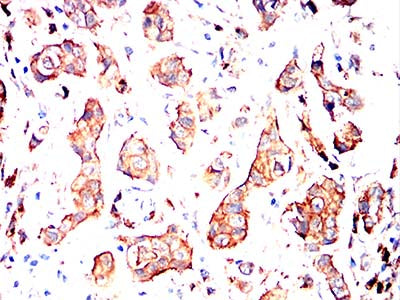

Immunohistochemical analysis of paraffin-embedded human cervical cancer tissues using MRP3 mouse mAb with DAB staining.